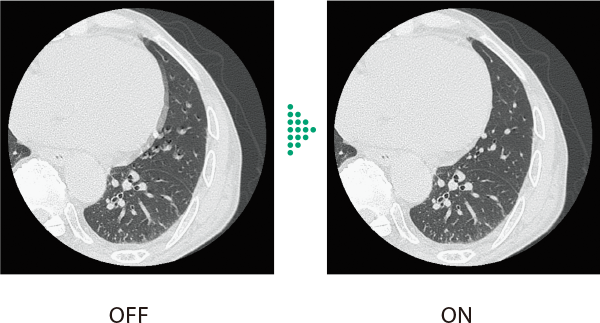

胸部領域全体で画像のブレを抑える

従来の胸部CT検査*1は、心拍動の影響や被検者の体動などにより画像のブレが発生し、診断が難しいケースがありました。Body StillShotは、収集したRawDataから被写体の動く方向と量を4次元的に算出し、動きによるブレの少ない画像を提供します。AI技術を活用して開発した画像再構成技術IPVとの併用も可能で、さらなる高画質化に寄与します。